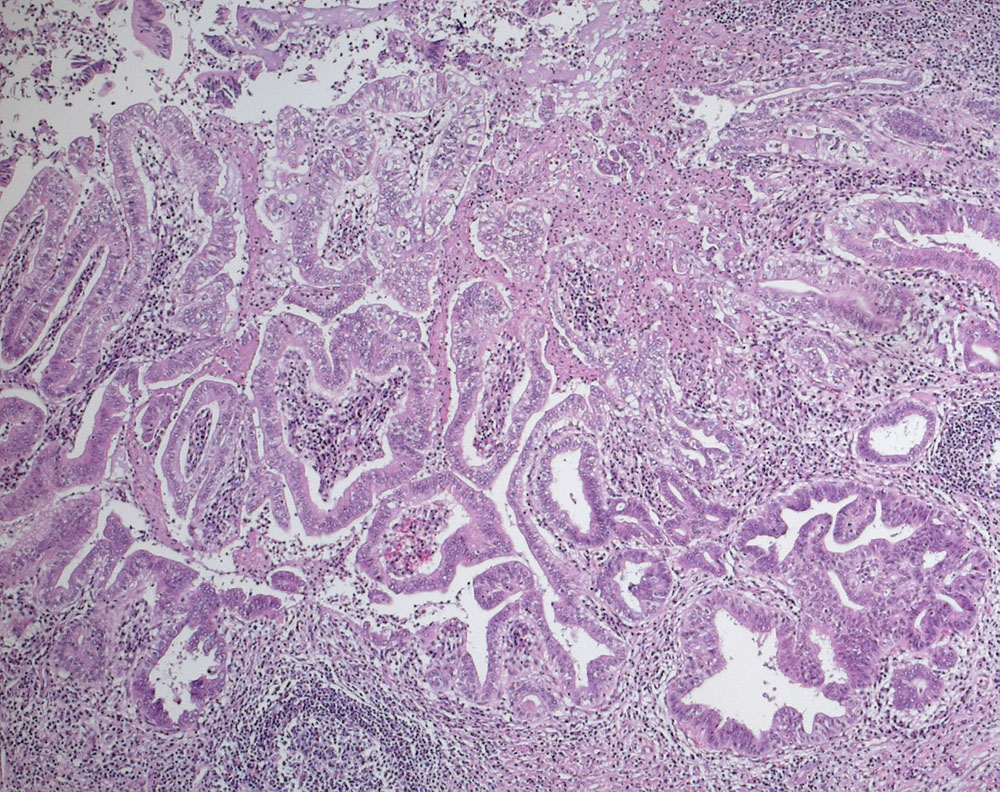

Intraduktale papilläre muzinöse Neoplasie mit mässiggradiger Dysplasie

Intraduktale papilläre muzinöse Neoplasie (IPMN), pankreatobiliärer Typ mit mässiggradier Dysplasie. Der Tumor bildet im Bereich des Ductus pancreaticus papilläre und glanduläre Strukturen ausgekleidet von zylindrischem Epithel mit mässiggradigen Atypien.

Maximaler Durchmesser 22mm, bis zur Papilla Vateri reichend. Im untersuchten Material keine Invasion nachweisbar.

Tumor des Ductus Wirsungianus